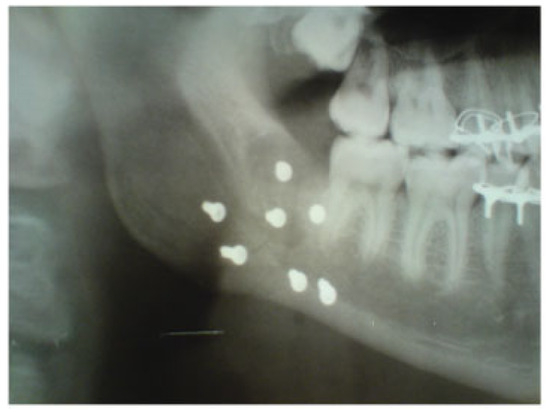

A 23-year-old patient was admitted to the Department of Oral and Maxillofacial Surgery at Lviv National Medical University with complaints of swelling of the cheek, intraoral bleeding, and “bad” bite associated with falling from a bicycle. After complete clinical and roentgenological examination, a diagnosis of traumatic fracture in the right mandibular angle area with fragment displacement and impaction of tooth no. 48 in the fracture line was established (Figure 6). He underwent removal of tooth no. 48 from the fracture line, open reduction, and internal fixation of the mandible with two HMWPE miniplates via combined intraoral and transbuccal approaches (Figure 7). A control X-ray obtained the day after osteosynthesis revealed perfect anatomical reduction and fixation of bone fragments (Figure 8). Temporary MMF was maintained for 3 days after osteosynthesis. The postoperative recovery was uneventful, and good mouth opening was achieved. The duration of the patient’s hospitalization was 8 days.

Figure 6. Fragment of orthopantomogram in a 23-year-old patient. Diagnosis was traumatic fracture of right mandibular angle with fragment displacement. Impaction of tooth no. 48 in the fracture line.